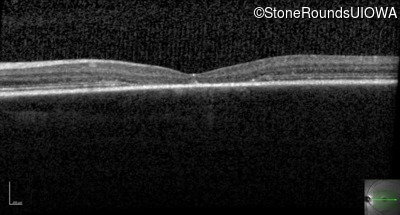

Age at visit: 13 years

This 13 year old male first had difficulty reading print and road signs in the past year.